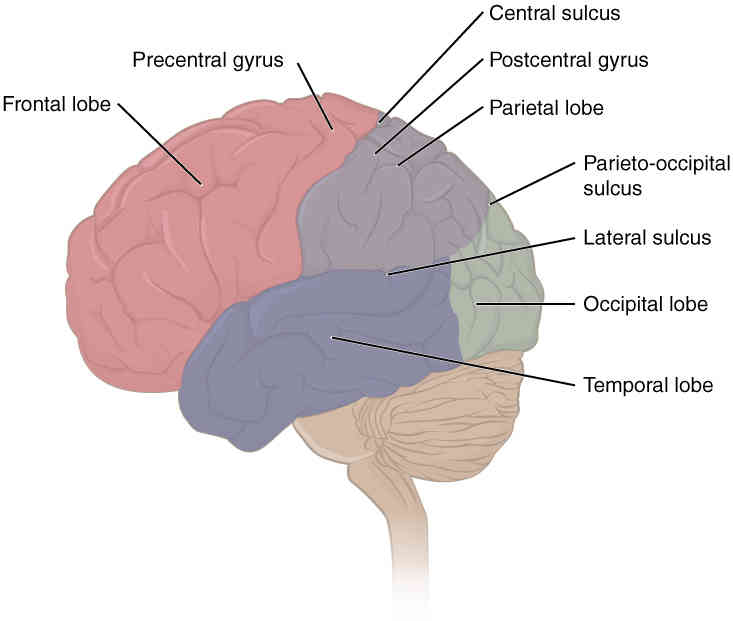

This page is under construction. For now, it is just a resource of the images found in the OpenStax Anatomy and Physiology Handbook. It wil slowly change into a revision tool. Each slide has a number. Use this to refer to the slide. When completed, it will have an unlabelled section, with labelled slides in parallel. On the unlabelled slides, write your answer and use the labelled slide to assess yourself. Keep track by also noting the number on each slide. Improvement at each attempt is important, more so than full marks on a first attempt.